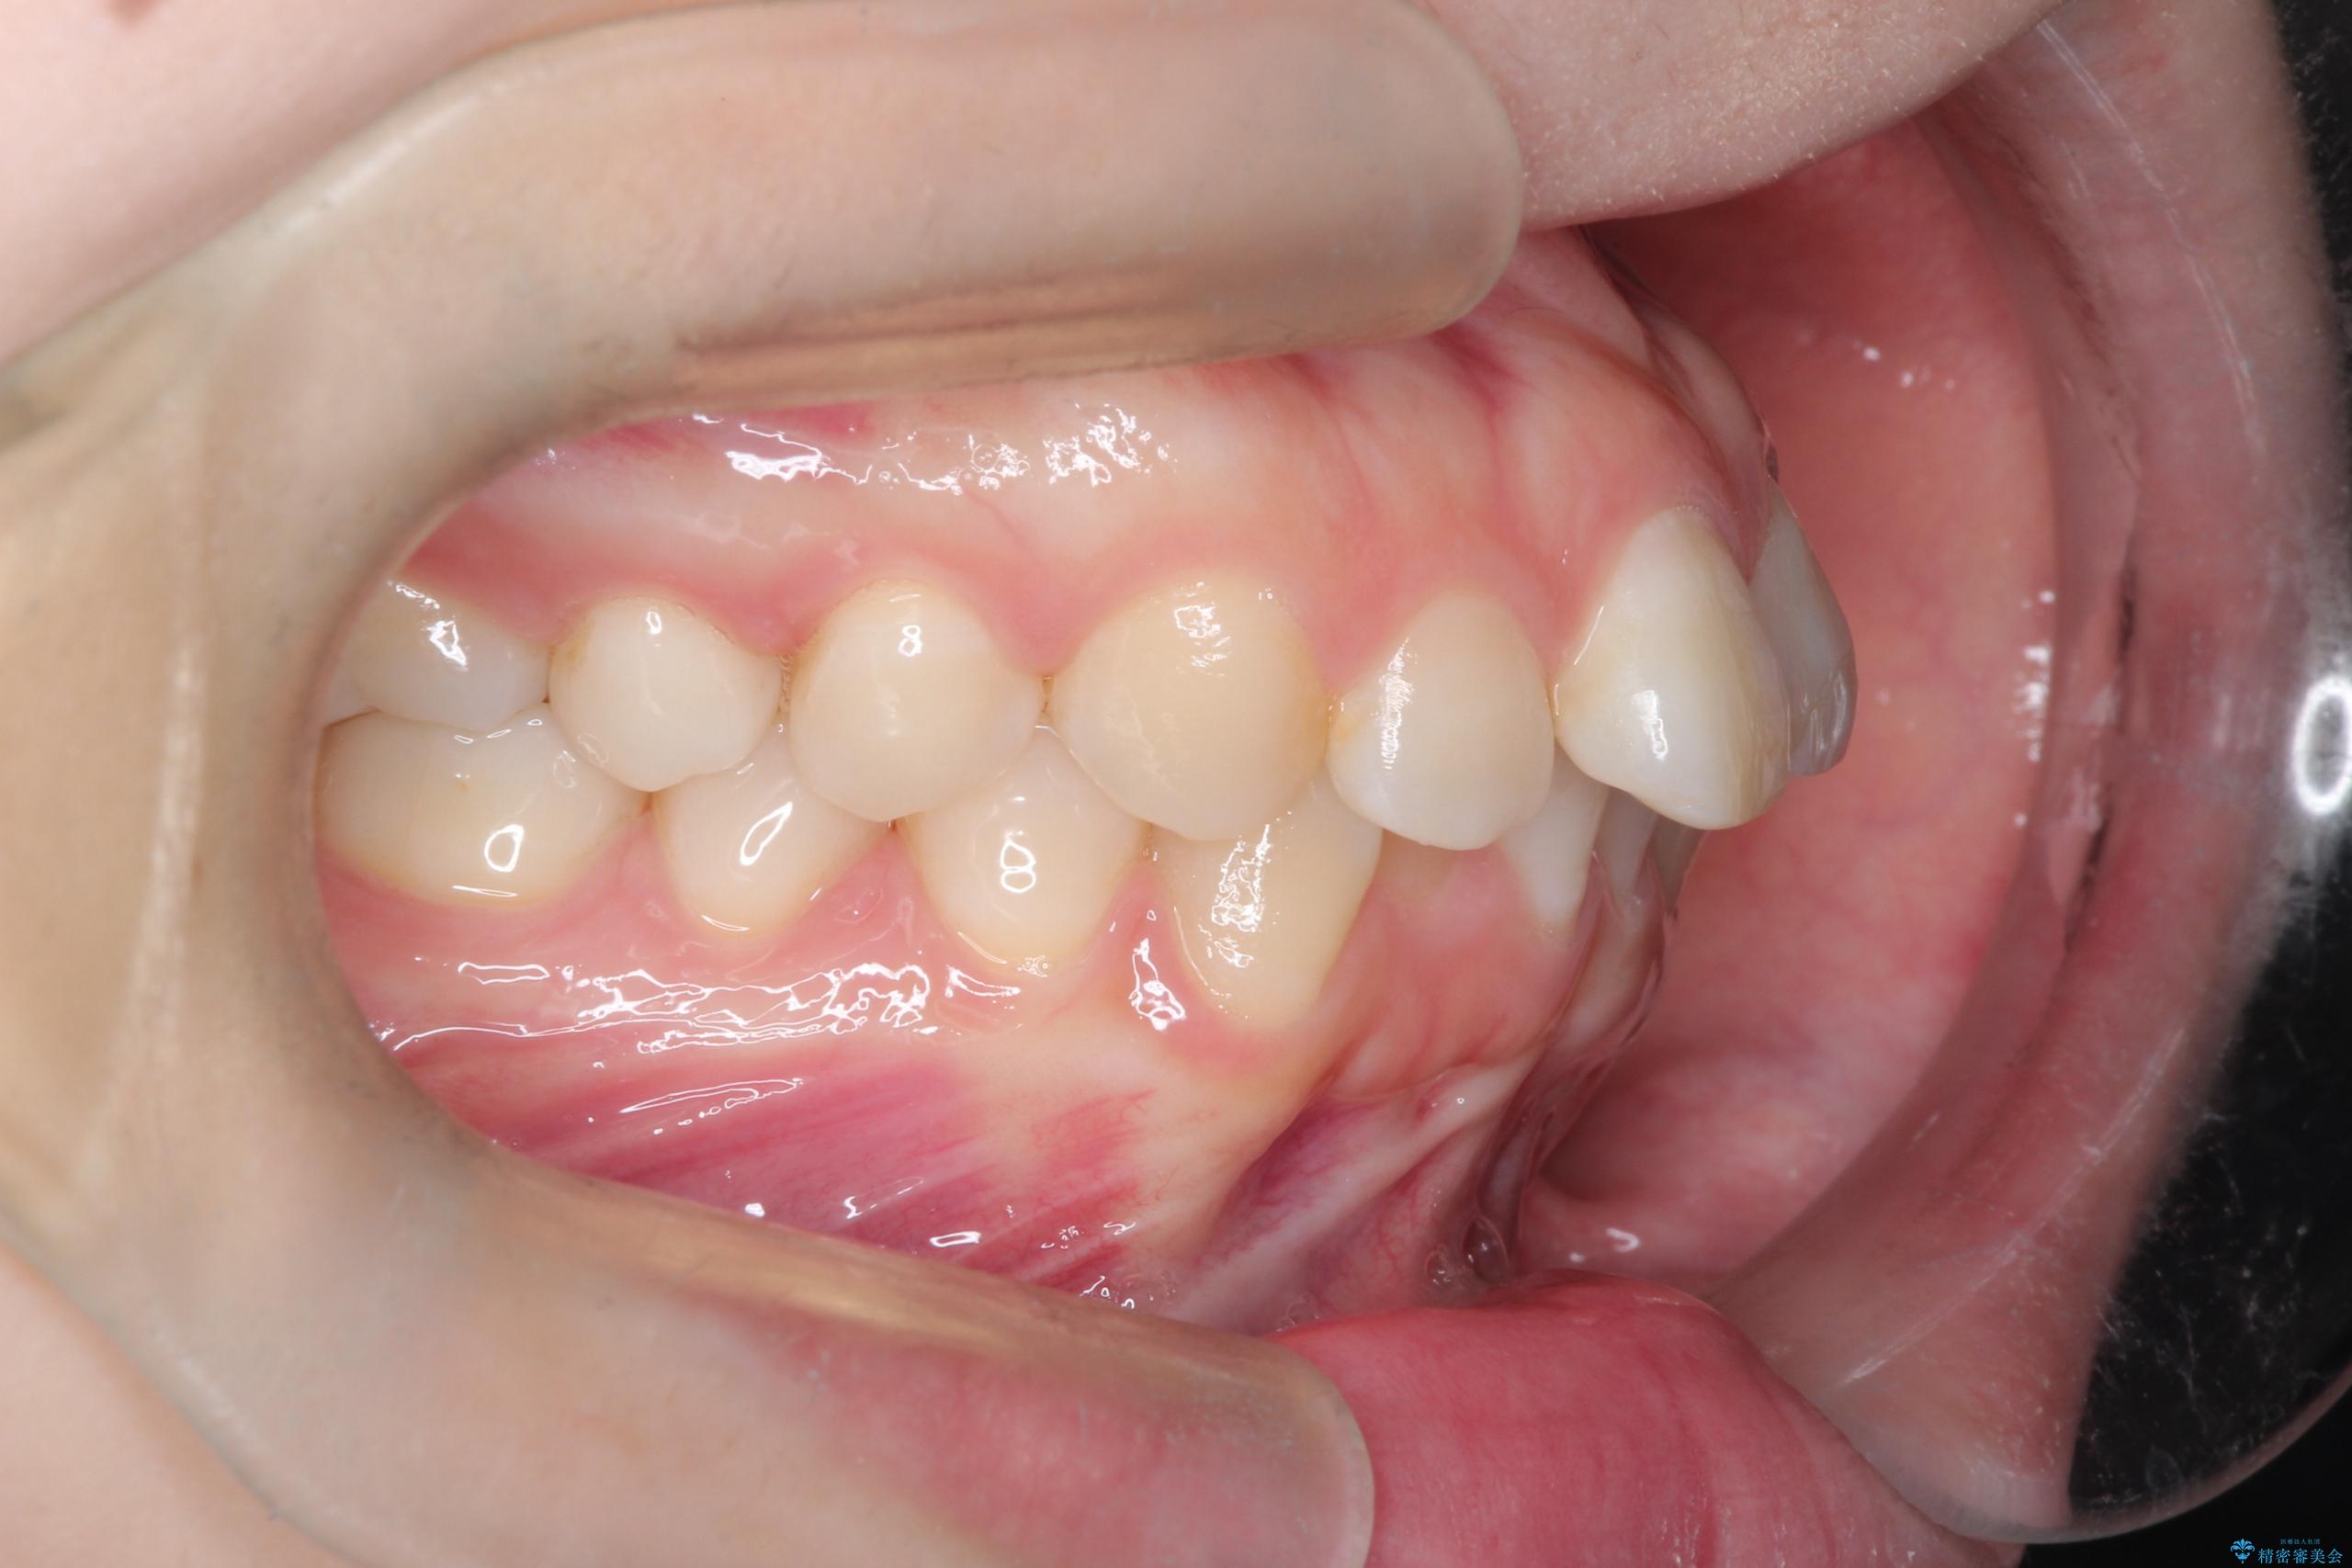

- 前歯のデコボコ(叢生)を気にされてご来院されました。精密な検査の結果、歯が並ぶスペースが不足していることが判明。患者様のご希望から、透明で目立ちにくいインビザライン(マウスピース矯正)による治療計画を立案しました。抜歯を避け、奥歯全体を奥へ動かす遠心移動という方法でスペースを確保し、前歯の叢生を解消することを目指します。

今回の矯正治療では、透明なマウスピース型の装置インビザラインを使用しました。この装置は取り外し可能で、日常生活で目立ちません。治療は、緻密に計算された計画に基づき、段階的に作製されたマウスピースを交換していくことで、奥歯から順に全体を後方へ移動させる遠心移動を実施。これにより、前歯を並べるための十分なスペースが確保され、デコボコが解消されました。抜歯することなく、機能的にも審美的にも整った美しい歯並びを獲得していただけました。